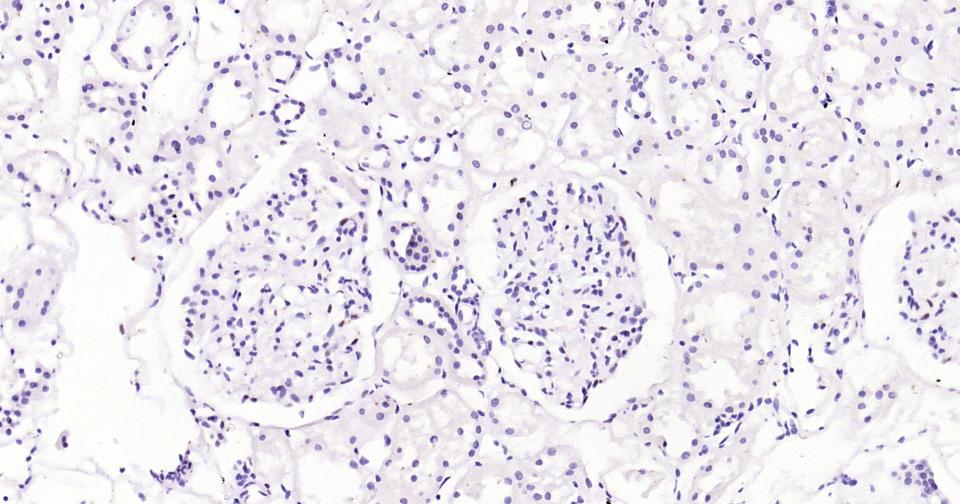

Paraformaldehyde-fixed, paraffin embedded Human Kidney; Antigen retrieval by boiling in sodium citrate buffer (pH6.0) for 15 min; Antibody incubation with WT1 Monoclonal Antibody, Unconjugated (bsm-60926R) at 1:200 overnight at 4°C, followed by conjugation to the bs-0295G-HRP and DAB (C-0010) staining.